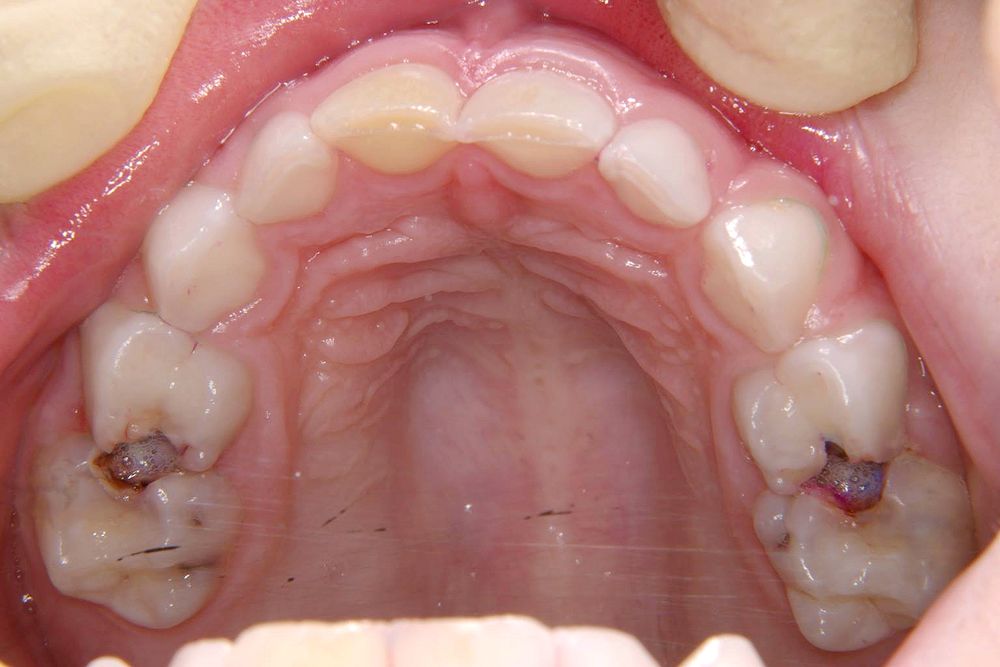

Carie No Dente De Leite, Cárie em Dente de Leite é necessário tratar | Ianara Pinho, 3.89 MB, 02:50, 24,219, Ianara Pinho Dentista - Implante dentário e Lente de Contato Dental, 2017-09-27T15:30:07.000000Z, 3, Por que tratar a cárie no dente de leite? - OdontoBebé, www.odontobebe.com, 1000 x 667, jpeg, WebSe a lesão de cárie não é tratada, as bactérias presentes podem atingir o canal do dente de leite e contaminar o germe do dente permanente, que está logo. WebA cárie é o resultado da corrosão causada pela liberação de ácidos da fermentação de partículas de alimentos e açúcares. Portanto, isso significa que ela é o., 20, carie-no-dente-de-leite, Ciência popular e notícias WebSe a lesão de cárie não é tratada, as bactérias presentes podem atingir o canal do dente de leite e contaminar o germe do dente permanente, que está logo. WebA cárie é o resultado da corrosão causada pela liberação de ácidos da fermentação de partículas de alimentos e açúcares. Portanto, isso significa que ela é o.

WebA cárie no dente de leite é causada principalmente pela falta de higienização correta, o exagero na ingestão de açúcar também pode contribuir. E é preciso tratar como. WebSó quem pode indicar o melhor tratamento para cárie no dente da frente é um dentista. Afinal, ele precisa avaliar diferentes pontos para chegar a essa conclusão.. WebSonhar com dente caindo significa que você pode estar passando ou logo irá enfrentar uma situação na qual se sentirá inferior. Terá receio das suas capacidades e. WebFutebol Dente de leite TV Tupi anos 70. 712 likes · 4 talking about this. Campeonato Paulista de Futebol Dente de Leite idealizado pelos Jornalistas Eli Coimbra, Roberto. WebMourão. A cantiga do Mourão se assemelha à história do telhado. Mas ela serve mais para crianças que não acreditam muito em fadas. Diz a lenda que se o. WebPara ajudar seus filhos a terem uma boa escovação e assim evitar a cárie no dente de leite, sempre mostre a eles quando você está escovando os dentes. Afinal,. WebSão muito importantes no desenvolvimento da fala na criança. São fundamentais na passagem da alimentação liquida para a alimentação sólida. O aparecimento da cárie no.

WebA cárie é uma deterioração da estrutura dentária causada por certos tipos de bactérias. Essas bactérias produzem ácidos que desmineralizam o esmalte do dente. Em casos. WebQuando o dente de leite é extraído precocemente, antes de sofrer o processo natural de perda de raiz, ele deixa um espaço que é ocupado pelos. WebOs dentes de leite podem e devem receber tratamentos preventivos como limpeza e aplicação de flúor no consultório. E, diante de uma cárie, eles também podem ser.